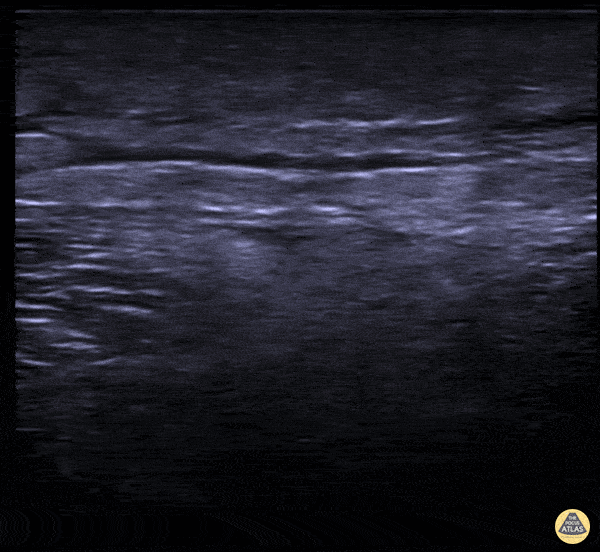

A 56-year-old male presented to the ED for left leg pain after sustaining puncture wound to the foot 4 hours prior arrival. An ultrasound was performed which demonstrated fluid within fascial layers with dirty shadowing consistent with subcutaneous air at the center of the image. Nicmarie Maldonado, MD PGY-2; Eddie G. Rodriguez, MD; Miguel Agrait, MD; Michelle Surillo, MD - Division of Emergency Ultrasound, St. Luke's Medical Center/PHSU, Ponce, PR